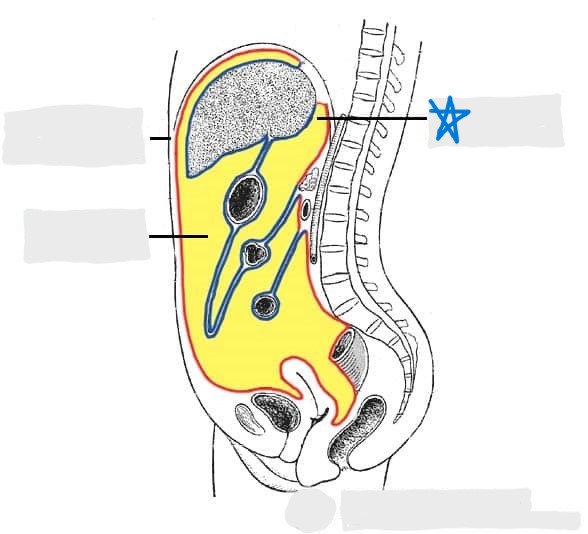

visceral peritoneum

parietal peritoneum

abdominal cavity

pelvic cavity